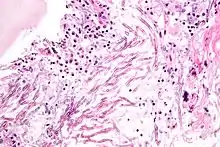

Les pathologies fongiques chez l'homme (souvent subdivisées en infections appelées mycoses superficielles, mycoses sous-cutanées et mycoses systémiques) sont étudiées par la mycologie médicale et combattues par les antimycosiques. « Le traitement des infections fongiques a été généralement moins efficace que celui des infections bactériennes, essentiellement parce que les champignons, sont des eucaryotes, et sont beaucoup plus semblables aux cellules humaines que ne le sont les bactéries. De nombreuses substances inhibant ou tuant les champignons sont de ce fait assez toxiques pour les êtres humains et ont donc un faible indice thérapeutique. En outre, la plupart des champignons ont un système de détoxication qui modifie de nombreux agents antifongiques, et en limitent l'efficacité. La plupart des antifongiques n'ont qu'une activité fongistatique tant que des applications répétées maintiennent de hauts niveaux d'antibiotiques non modifiés. Néanmoins, quelques substances sont utiles dans le traitement de nombreuses mycoses sévères[6] ».

Près de 300 espèces fongiques connues sont impliquées dans les mycoses humaines[7]. Les maladies opportunistes systémiques dues à ces agents infectieux sont rarement contagieuses, contrairement aux maladies virales et bactériennes. Elles sont à l'origine de 1,6 million de morts par an à l'échelle mondiale[8], soit plus que celles dues aux animaux les plus mortels pour l'homme et « presque autant que la tuberculose (1,7 million), la maladie infectieuse la plus meurtrière au monde[9] ». Les principales infections fongiques sont les cryptococcoses avec une mortalité associée de 20 à 70 %, suivies par les candidoses (mortalité associée de 46 à 75 %), les pneumocystoses (20 à 80 %), les aspergilloses (30 à 95 %) et les histoplasmoses (28 à 50 %)[10].